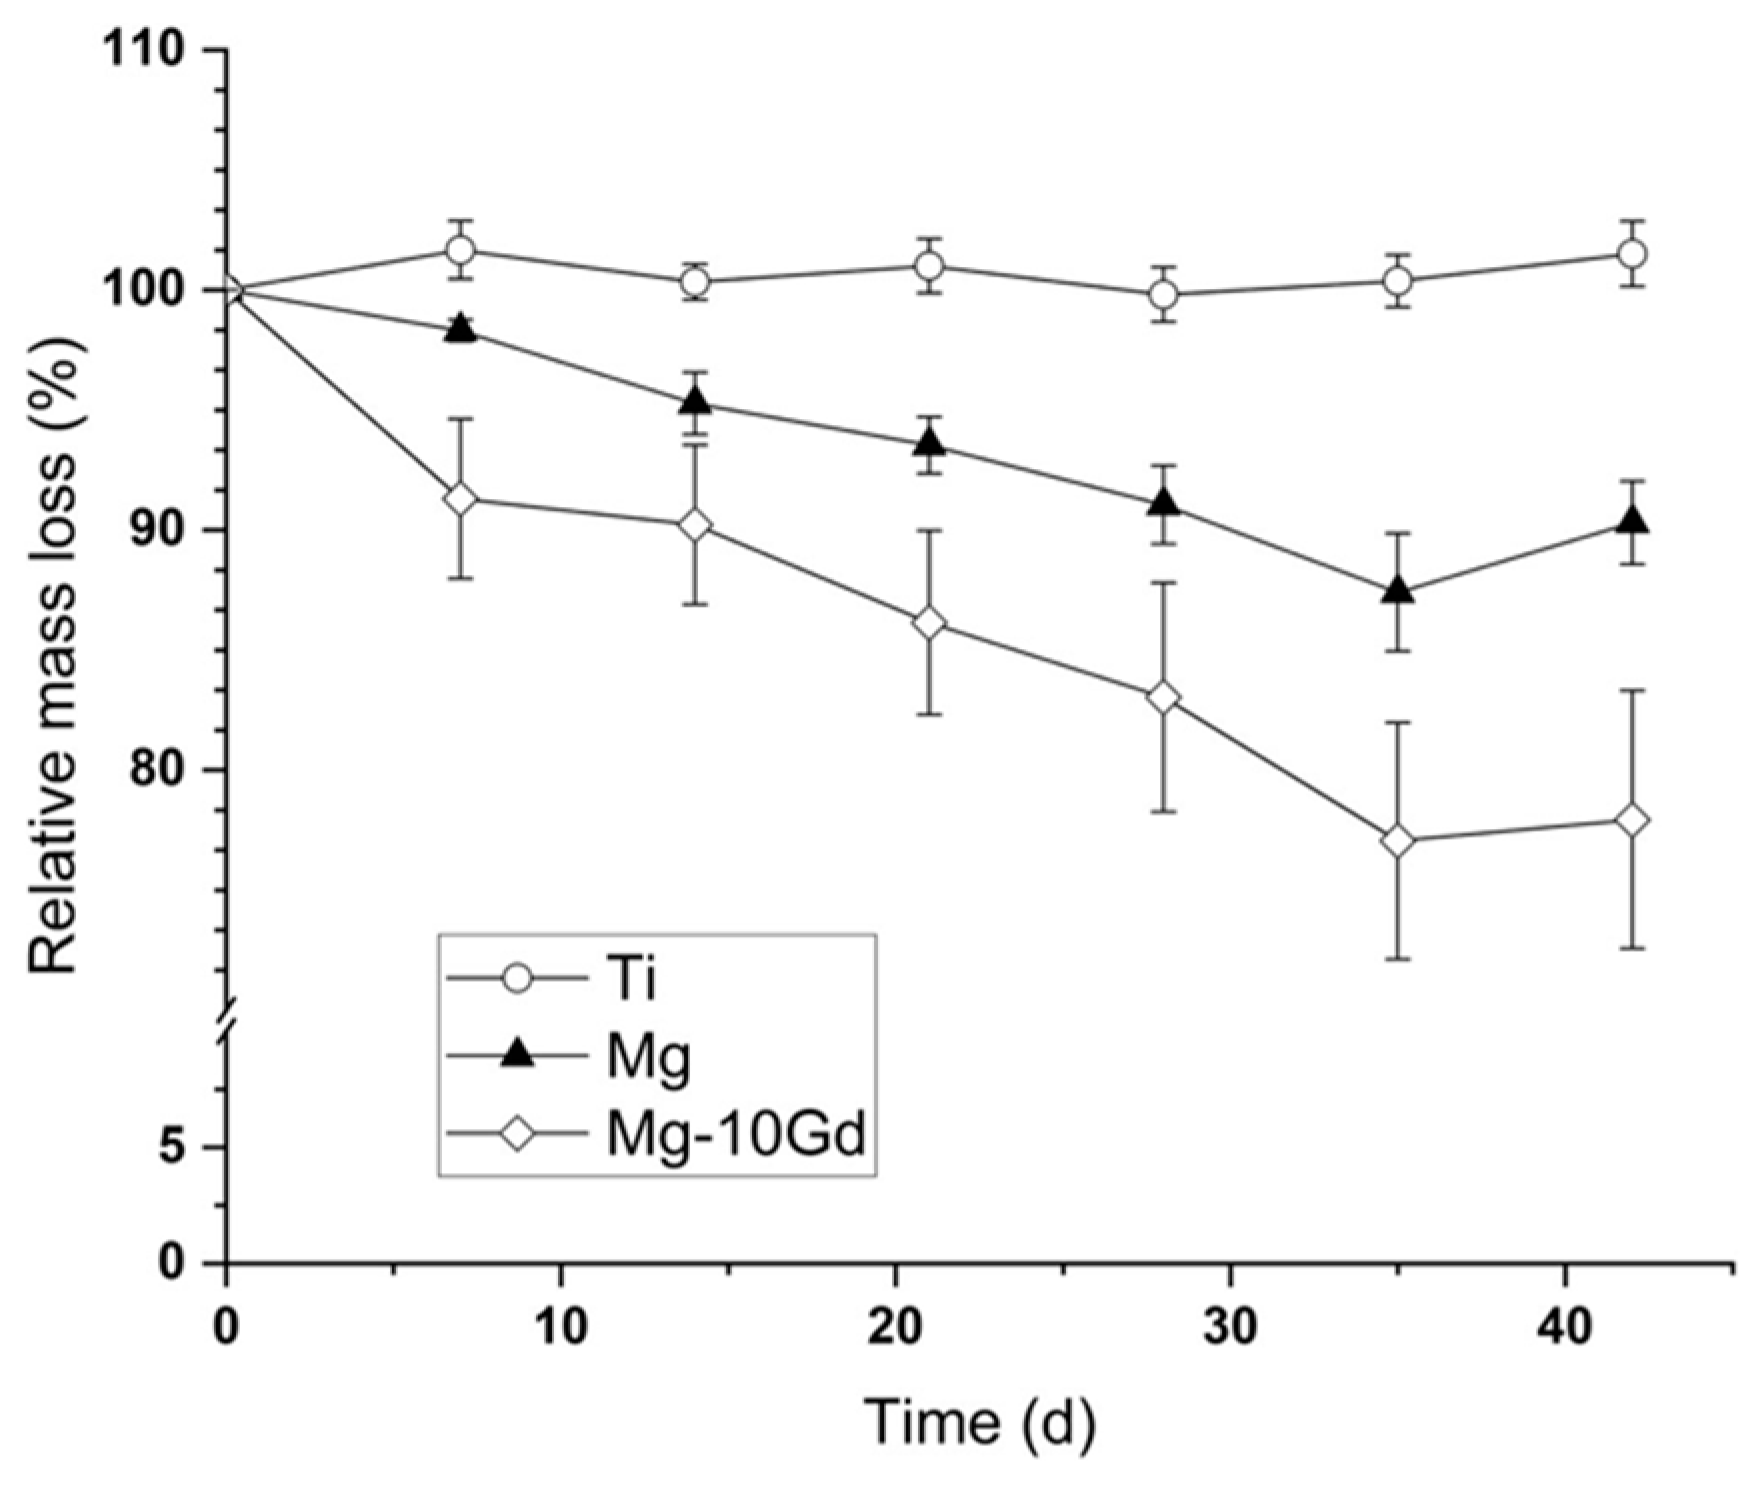

- Zeller-Plumhoff, B.; Malich, C.; Krüger, D.; Campbell, G.; Wiese, B.; Galli, S.; Wennerberg, A.; Willumeit-Römer, R.; Wieland, D.F. Analysis of the bone ultrastructure around biodegradable Mg–xGd implants using small angle X-ray scattering and X-ray diffraction. Acta Biomater. 2020, 101, 637–645. [Google Scholar] [CrossRef] [PubMed]

- Bian, D.; Deng, J.; Li, N.; Chu, X.; Liu, Y.; Li, W.; Cai, H.; Xiu, P.; Zhang, Y.; Guan, Z.; et al. In Vitro and in Vivo Studies on Biomedical Magnesium Low-Alloying with Elements Gadolinium and Zinc for Orthopedic Implant Applications. ACS Appl. Mater. Interfaces 2018, 10, 4394–4408. [Google Scholar] [CrossRef]

- Helmholz, H.; Will, O.; Penate-Medina, T.; Humbert, J.; Damm, T.; Luthringer-Feyerabend, B.; Willumeit-Römer, R.; Glüer, C.; Penate-Medina, O. Tissue responses after implantation of biodegradable Mg alloys evaluated by multimodality 3D micro-bioimaging in vivo. J. Biomed. Mater. Res. Part A 2021, 109, 1521–1529. [Google Scholar] [CrossRef]